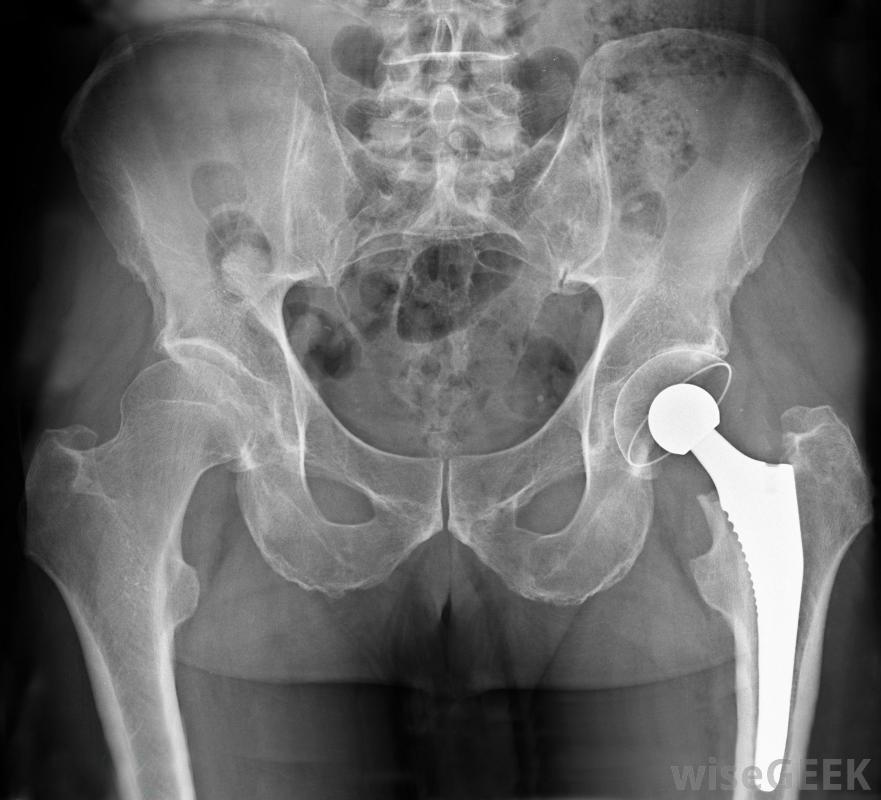

人工关节是一种治疗设备。对于视力或听力有轻微损伤的人,治疗设备如助听器或眼镜可以帮助他们获得显著的视觉和听觉的改善,即使在严重的情况下,这些设备也可以大大提高用户执行日常任务的能力,例如阅读、看电视,或者进行对话。也可以为那些完全丧失听力或视力的人提供辅助设备。这些设备可能包括为盲人设计的文本语音转换程序和盲文书,以及为聋哑人提供的封闭字幕技术。尽管这些设备不能恢复任何失去的感觉,它们允许用户参与他们可能不得不避免的活动。

患者辅助设备包括手杖许多不同类型的治疗设备被用来治疗那些身体上有缺陷的人,这些障碍会抑制他们的行走能力。拐杖和手杖可以帮助那些有暂时或轻微损伤的人,而步行机和轮椅可用于那些有更严重限制的患者。人工关节可以代替患者受损的现有关节,以提供更好的整体活动能力。最常见的程序包括膝关节或髋关节置换。物理治疗设备,包括按摩台、举重机,甚至热水浴缸,可用于帮助患者在手术或事故后恢复活动能力。